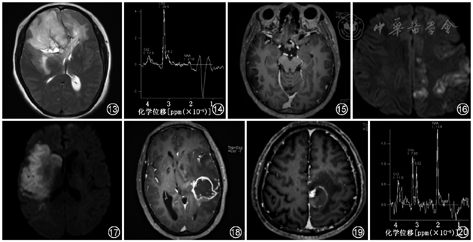

好发位置及肿瘤CT表现与OD相似。常有结节状、团块状或脑回样钙化(图7),瘤内囊变多见,出血、水肿、坏死较Ⅱ级多见(图8),邻近颅骨可扩大、重塑、侵蚀。MRI表现为病灶边界不清楚,信号不均匀,T1WI呈不均匀低信号(图9,10),T2WI呈不均匀高信号,FLAIR序列呈不均匀高信号,DWI扩散不受限或轻度受限。增强扫描强化方式多变,AO较低级别OD强化更多见(图11,12),环状强化少见,若出现常提示预后不良。由于肿瘤呈弥漫浸润(图13),可在异常信号区外发现肿瘤细胞[2]。MRS表现为Cho/Cr升高,NAA峰减低,1.33 ppm可见脂质峰(Lip)/乳酸峰(Lac)(图14)。PWI表现为rCBV明显增高,能帮助鉴别Ⅱ级与Ⅲ级少突胶质细胞瘤和引导活检[9, 10]。

发病年龄在20岁以前,好发于颞叶皮质,边界清楚,信号不均匀,少见钙化。强化方式以无强化(图15)或轻度强化多见。

任何年龄均可发生,临床起病急,病灶累及灰白质,影像表现T2WI呈明显高信号,DWI扩散受限(图16),可见散在强化灶。

发病年龄较大,临床有脑血管病的病史,起病急,病灶位于典型的血管分布区,如大脑中动脉、大脑前动脉、大脑后动脉,若在急性期或亚急性期,病灶累及灰质和白质,常呈楔形,病灶内无钙化,DWI扩散受限(图17);若在亚急性期,病灶呈脑回样强化。

胶质母细胞瘤属于WHO Ⅳ级肿瘤,恶性程度相对较高,发病年龄相对较大,发病部位较深,信号不均匀,95%有坏死核心,出血多见,增强呈明显花环样强化(图18),多有子灶。MRS和DWI特征表现有助于两者的鉴别。Cho/NAA及Cho/Cr比值较AO更高,DWI肿瘤实体部分的信号也高于AO。